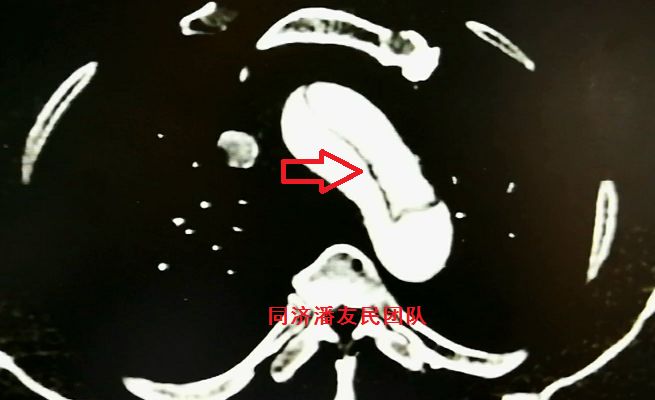

该患者之所以腹痛症状明显,是因为夹层在腹主动脉段撕裂更加严重 ,真腔几乎压闭了。

腹腔干动脉由真假双腔供血,真腔狭窄(图9),肠系膜上动脉由假腔供血,真腔完全压闭了(图10),双肾动脉也由假腔供血(图11)。由于腹腔脏器缺血导致脾脏、左肾部分梗死。因此,患者主要症状是腹痛,而胸痛不明显。这可能也是导致诊断分型不准确的原因之一。

图9:CTA显示主动脉夹层累及腹腔干动脉,真腔狭窄(红箭头所示),同时显示脾脏部分梗死(红星形所示)

图10:CTA显示肠系膜上动脉由假腔供血(红箭头所示),真腔压闭,左肾及脾脏梗死(红星形所示)

图11:CTA显示双肾动脉由假腔供血(红箭头所示),左肾梗死(红星形所示)